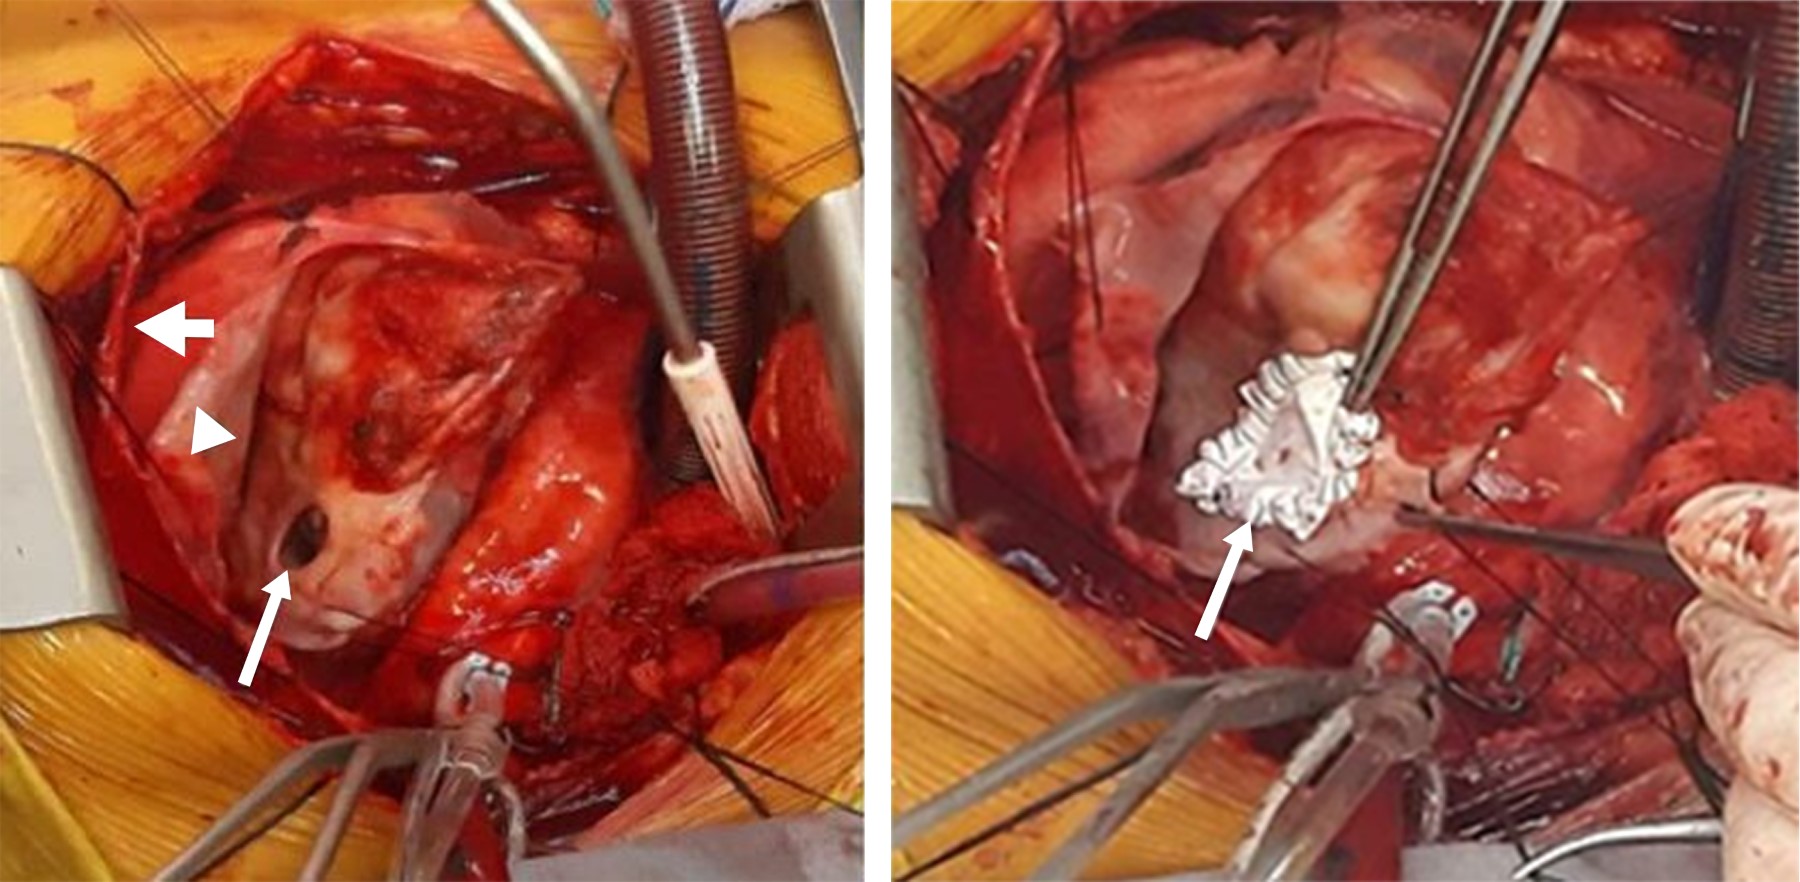

La paciente ingresó a quirófano a las 8 am, el monitoreo incluyó electrocardiograma en DII y V5 continuo, presión arterial invasiva en la arteria radial derecha, oximetría de pulso, presión venosa central, gasto urinario, temperatura esofágica y rectal. Se realizó inducción anestésica endovenosa con fentanilo, rocuronio y etomidato, se intubó con cánula 7.5 mm DI, se mantuvo con oxígeno al 80% y desflurano, además de una infusión de fentanilo. En fase pre bypass se tomó tiempo de coagulación activado (TCA) inicial 153 segundos y además se da apoyo con norepinefrina y levosimendán por perfil hemodinámico que evidenció síndrome de bajo gasto, posteriormente se administra heparina y se da inicio a circulación extracorpórea en asistencia circulatoria para completar la disección quirúrgica (Figura 4), luego pinzamiento cruzado de la aorta y el paro cardíaco con solución cardiopléjica fría para realizar la resección del pseudoaneurisma ventricular y la reparación con parche de politetrafluorotileno (PTFE), hipotermia a 28 oC. En la fase de circulación extracorpórea (CEC) se inició perfusión de nitroprusiato para mantener presión arterial media (PAM) < 70 mmHg el cual se suspendió al salir de bomba. Después de un pinzamiento de 102 minutos se despinza la aorta con normotermia, sale a asistolia, se conecta a marcapasos epicárdico, del cual depende durante 15 minutos, después queda marcapasos centinela. Posterior a salida de CEC, se inició apoyo con perfusión de dobutamina y se continúa apoyo con norepinefrina y levosimendán, se administró protamina 450 mg, se transfunden dos unidades de concentrados eritrocitarios, cuatro de plasma fresco congelado, una aféresis plaquetaria y se administra la sangre de recuperador celular (690 mL), se toma TCA final 131 segundos. Al término de acto quirúrgico, la paciente se trasladó a la unidad de cuidados intensivos con RASS -4 bajo ventilación asistida con sistema bolsa-válvula-mascarilla adaptado a tubo endotraqueal, O2 suplementario, TA 128/62 FC 96 lpm SpO2 99%, perfusión de norepinefrina a 0.03 μg/kg/min, levosimendán a 0.1 μg/kg/min, dobutamina a 4 μg/kg/min.

Figura 4